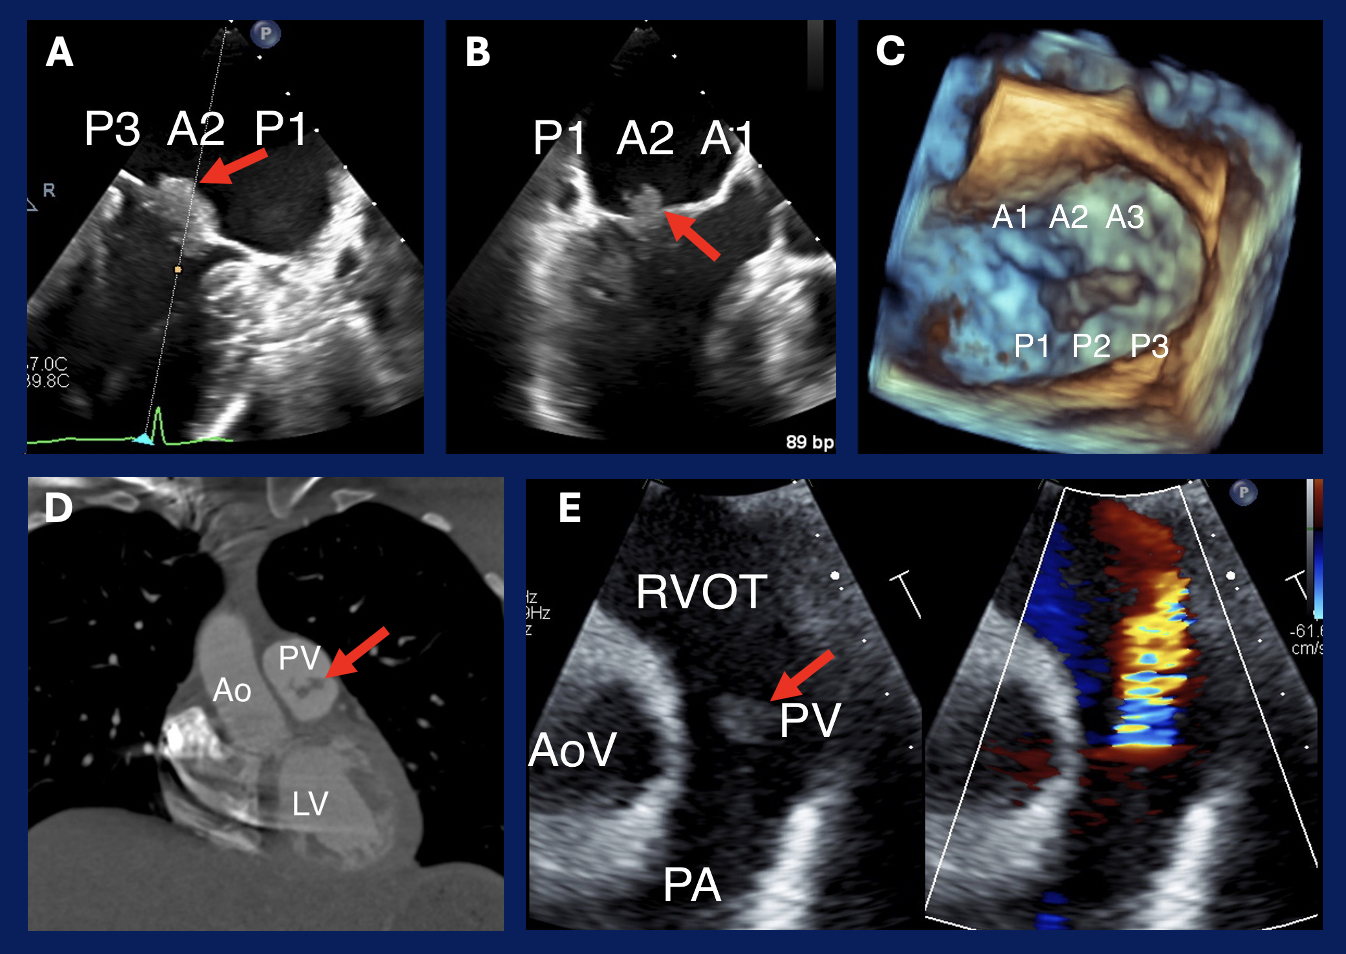

Abstract Body (Do not enter title and authors here): A 42-year-old female with SLE, lupus cerebritis with related seizure disorder, and mesenteric venous thrombosis on warfarin initially presented for syncope. Acute stroke workup was negative, and syncope was attributed to possible brief seizure. Six months later, the patient was evaluated by cardiology for hypertension diagnosed during hospitalization. She reported no further syncope, but exam revealed a 3/6 holosystolic murmur. Subsequent TTE identified severe MR with primary MV degeneration and LVEF >60%. A TEE confirmed severe MR with myxomatous MV leaflets and moderate-sized nonmobile vegetations attached to the atrial side of A2 and P2 of the MV. Subsequent infectious workup including serial blood cultures were negative. The patient was diagnosed with non-bacterial Libman-Sacks endocarditis (LSE). Given a lack of symptoms and plan to resume immunosuppressive therapy and continue her anticoagulation (AC), surgical intervention was initially deferred with close follow-up.

The patient continued to endorse worsening headaches and brain MRI revealed new chronic small ischemic strokes. One morning, the patient noted sudden aphasia and presented to the ED. Stroke workup revealed an acute ischemic stroke with total left M2 occlusion of her MCA, and she underwent thrombectomy. Cerebral angiogram further revealed FMD. Given ongoing embolic phenomena, likely from LSE, she underwent MVR with mechanical valve and LA appendage ligation and continued mycophenolate and warfarin. Two months postoperatively, the patient remained asymptomatic with normal prosthetic valve function and neurologic status. However, evaluation for extracranial FMD with CTA revealed interval development of PV vegetations. These lesions and moderate PR were confirmed on TTE.

Discussion: While response to immunosuppressive therapy and AC has been reported to improve early-phase LSE, this patient continued to experience thromboembolic events resulting from LSE vegetations while on mycophenolate and warfarin. Despite continuing these therapies after MVR, she later developed PV vegetations and PR. Pulmonary valve involvement is rare in LSE, and development of new disease while on recommended medical therapy represents unusual disease progression.